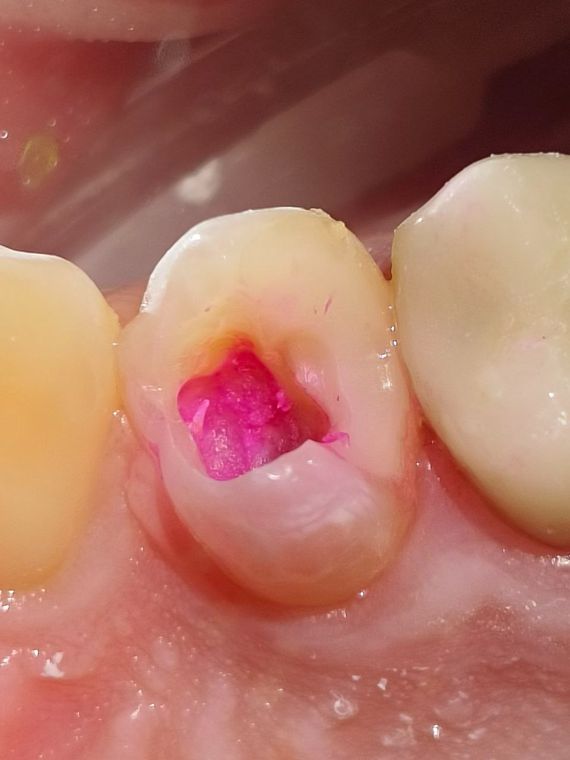

Во время лечения

При вскрытие эмали зуба, визуализируется кариозные ткани КИД (кариес инфицированный дентин)

окрашивание

Так же видно что ткани размягчины, и легко убираются ручными инструментами. Полость очень обьемная и глубокая

Мягкий дентин

В данном случае темная ткань это - CAD дентин - это часть зуба, которая повреждена кариесом. Такие ткани допустимо сохранить, для того чтобы не депульпировать зуб и оставить его "живым"